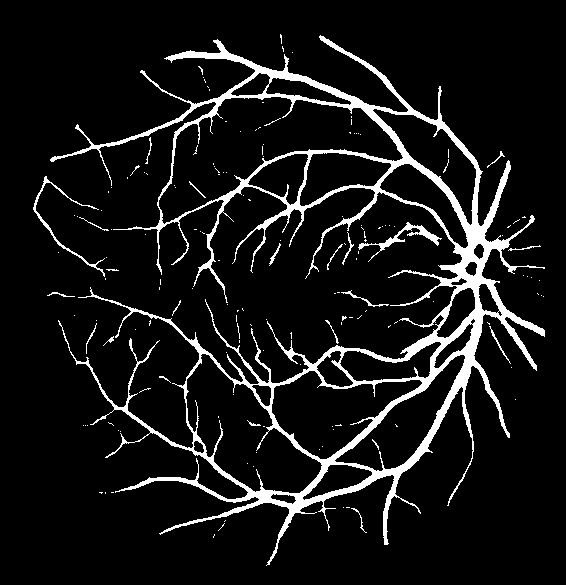

Refer to caption

(a) Original image

(b) Ground truth

(c) Level-I balancing

(d) Level-II balancing

(e) Original image

(f) Ground truth

(g) Level-I balancing

(h) Level-II balancing

Figure 6: Visual results after level-II balancing.

Impact of Level-II Balancing: This section analyzes the impact of applying Level-II balancing on top of Level-I balancing to the same sample images as in the previous sub-section. Specifically, the outcomes of applying Level-I and Level-II balancing are compared and graphically demonstrated in Figure 6. The application of Level-II balancing results in a significant performance boost over Level-I balancing, as indicated by higher values of all performance measures. Similarly, Figure 6 shows the visual outcomes of Level-II balancing for the sample DRIVE images along with their ground truths. The output segmentation masks show the detection of thin retinal blood vessels much closer to the ground truth binary mask than the images for Level-I balancing. The red rectangle is highlighted as a focus area for conveniently comparing the results. It can be concluded from comparing the results that Level-II balancing detects most of the vessel’s pixels, especially thin vessels, thereby significantly improving the sensitivity.